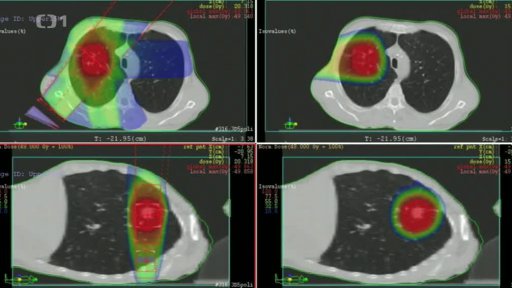

Protonové centrum na léčbu rakoviny bez pacientů

Protonové centrum v Praze na Bulovce je otevřené od loňského prosince. Supermoderní klinika na léčbu rakoviny má však pouze dva pacienty. A jejich počet se jen tak nezvýší. Zařízení za více než čtyři miliardy nemá smlouvu se zdravotními pojišťovnami v čele s VZP. Ta se jejímu uzavření brání. Nucený správce VZP totiž před lety zavázal pojišťovnu k placení nečekaných astronomických výdajů bez vědomí správní rady a za značně podezřelých okolností. Podívejte se na reportáž Anety Snopové.